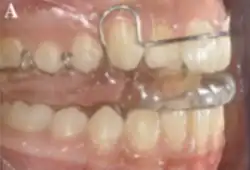

These appliances such as seen in Figure 3 work by enhancing forward growth of the mandible, which helps to correct the misalignment between the upper and lower jaws. This functional approach to treatment is designed to be efficient and effective in addressing Class II malocclusion.[1] Reverse Twin Block appliance can be used in addressing Class 3 malocclusion.